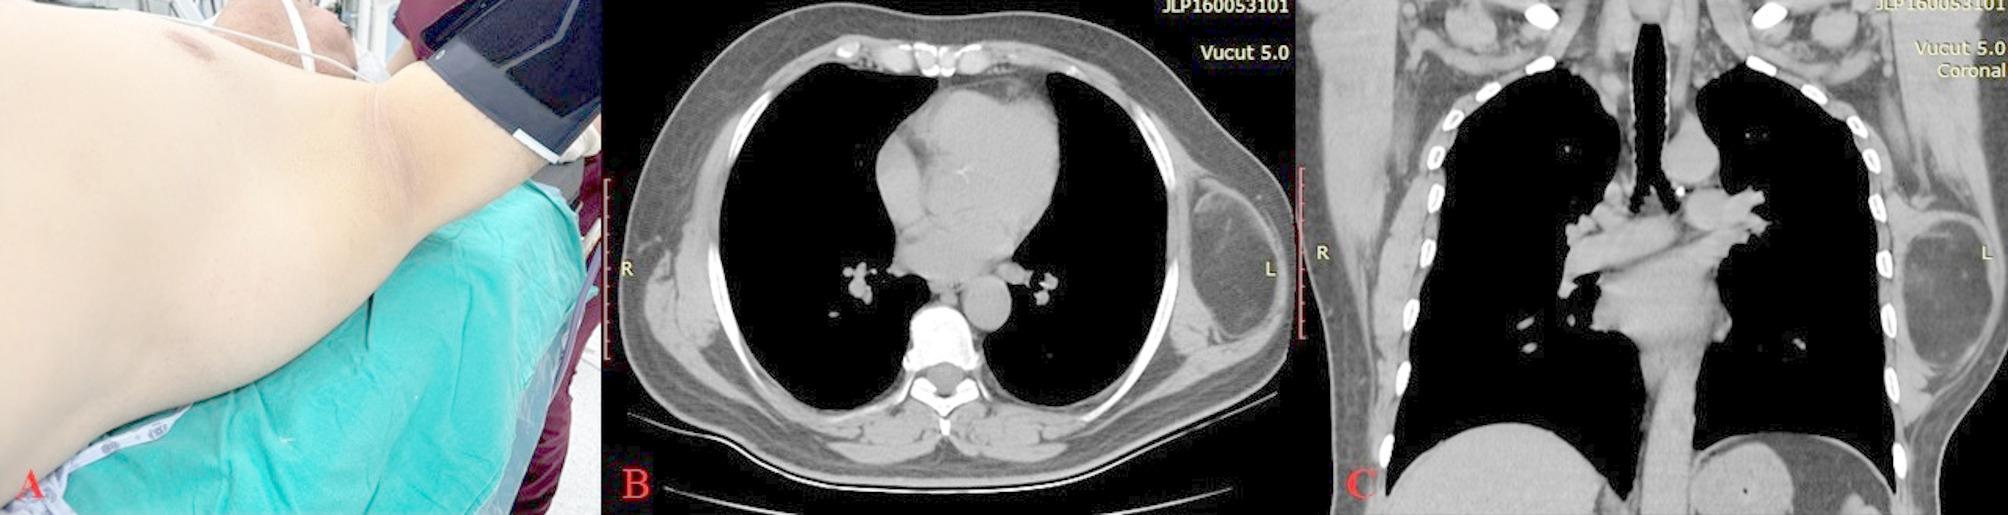

Case presentation: A 51-year-old male patient was admitted to the hospital with pain, numbness, and tingling in his left arm that started three months ago. A mass measuring approximately 10 × 10 cm was found in the left lateral thoracic wall, in the region just inferior to the axilla and along the lateral border of the scapula. When the patient was in the supine position, the mass was observed to migrate to the axillary region. When the patient leaned forward, it was observed that the mass shifted towards the upper part of the pectoral muscle. There was paraesthesia and tingling in the fingertips of the left hand, however, muscle strength was normal. Adson's and Wright's tests were positive. Considering the symptoms in the left upper extremity, we decided to excise the lesion. On postoperative day one, the patient stated that the pain and tingling in the left extremity had significantly decreased. We observed that neurological complaints significantly decreased, and oedema regressed in the first postoperative month. In the third postoperative month, the patient stated that he had no complications.